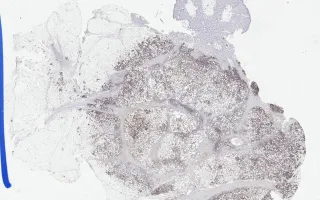

Soft Tissue, Subcutaneous panniculitis-like T-cell lymphoma, CD8 stain

This is a rare form of primary cutaneous T-cell lymphoma, predominantly affecting the subcutaneous fatty tissue. It is a cytotoxic T-cell lymphoma that preferentially involves subcutaneous tissue and expresses TCR-αβ. The dense lymphoid infiltration primarily involves the subcutaneous adipose tissue. Close look at the malignant cells reveal obvious atypia, with pleomorphism and numerous mitotic figures.

Demonstration of TCR-αβ is important, considering the differential diagnosis of primary cutaneous γδ T-cell Lymphoma. Mature T-cell phenotype is observed, with aberrant loss of CD5, CD7, and CD2 (in decreasing order). The majority of cases will show CD8 positivity.

This slide shows CD8 stain. See Related Content for H&E, CD3, CD7, and TCR beta stains.